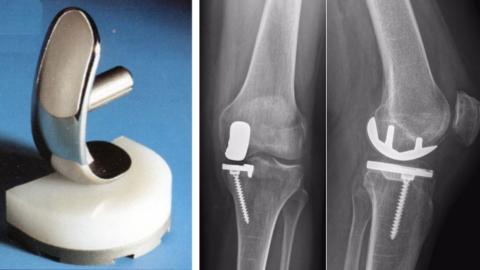

Les chirurgiens orthopédiques du CHU se forment à une meilleure pose des demi-prothèses du genou

Les pathologies orthopédiques du genou sont plus fréquentes sous nos latitudes. Le recours à des prothèses plus petites offrent...